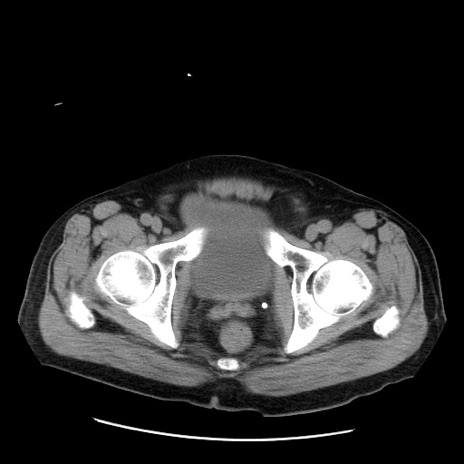

症例20(横断像)

【症例】 60歳代男性

【主訴】 腹部膨満、嘔吐

【現病歴】5日前頃より倦怠感を認め食事量減少し4日前の朝嘔吐、食事摂取困難となった。 3日前近医受診し点滴施行され整腸剤などを処方された。 当日他院を受診し、腹部膨満著明、炎症反応の上昇(CRP10.8、WBC11200)あり、紹介受診となる。

【身体所見】 意識JCS1 受け答えがはっきりしないBP 111/57mHg、 P 67bpm、、BT35.2°C、SpO2 97%(RA)、 腹部:膨隆、打診で鼓音あり、全体的に圧痛有り、腸蠕動音(-)、反跳痛ははっきりせず。

【データ】WBC 11400、CRP 14.20